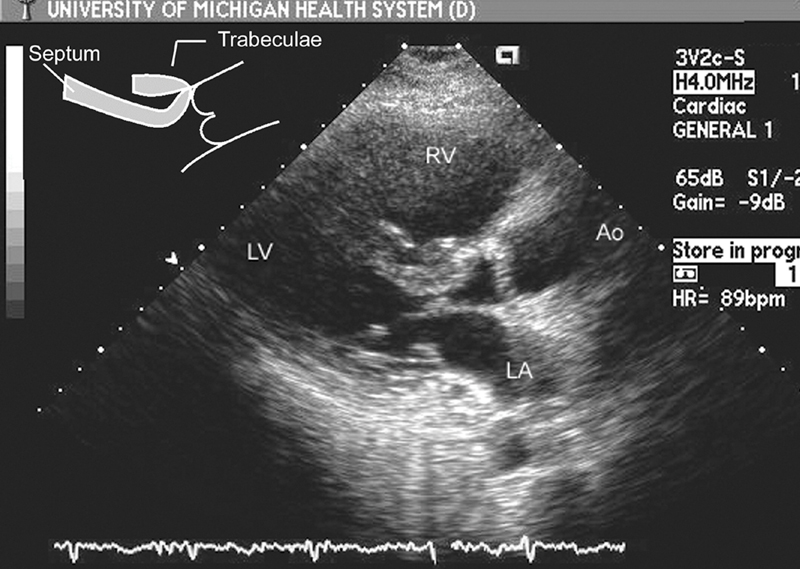

فحوصات تشخيصية لبعض امراض القلب والشرايين التاجية